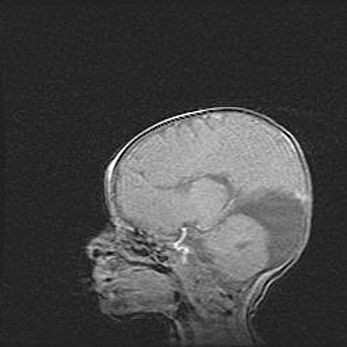

Аномалия Денди-Уокера. Признаки гипоплазии мозолистого тела.

Возраст: 5 месяцев 3 дня

Вес: 5550 г

Пол: мужской

Окружность головы: 39 см

Срок гестации: 40 недель

Аномалия Денди-Уокера – это порок развития головного мозга, для которого характерна триада симптомов: гипотрофия или аплазия червя мозжечка и/или полушарий мозжечка, расширение четвёртого желудочка с формированием ликворной кисты задней черепной ямки, гипертензионная гидроцефалия различной степени.

Гипоплазия мозолистого тела относится к дефектам внутриутробного этапа развития мозговой ткани, возникающим в процессе закладки структур головного мозга, что происходит на начальных этапах развития эмбриона.